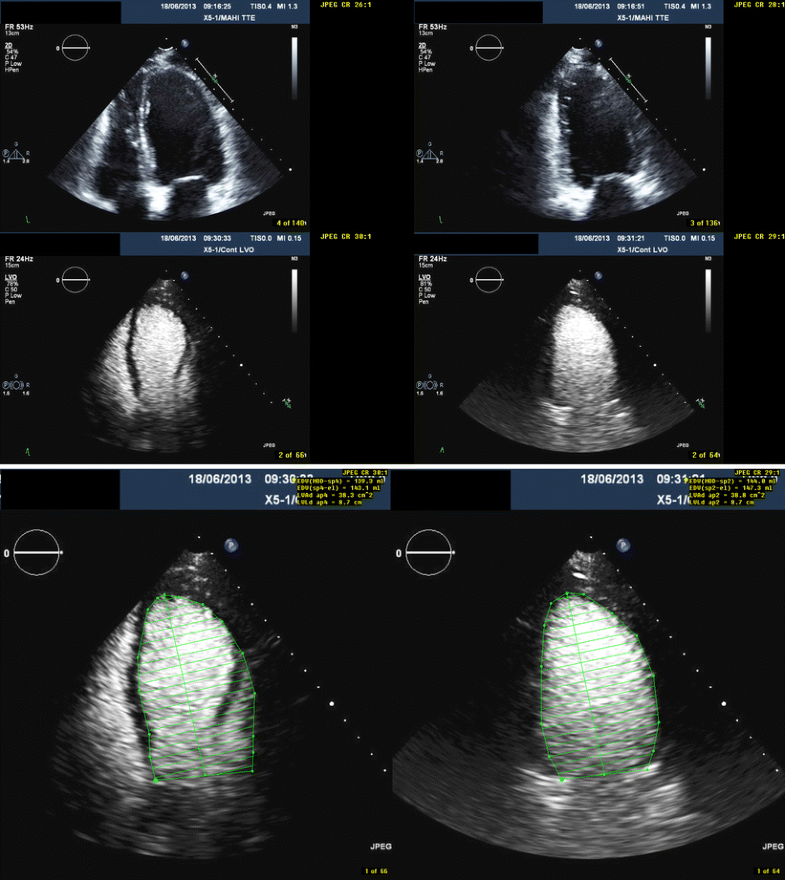

Transthoracic echocardiogram performed during first hospitalization How Is An Echocardiogram With Contrast Performed During a contrast echocardiogram a harmless substance called a contrast agent is injected into your bloodstream. We will use this to inject the special dye (known as contrast). A small tube called a cannula will be inserted into one of the veins in your arm. An echo is a scan that uses ultrasound (sound waves) to produce pictures of the. How Is An Echocardiogram With Contrast Performed.

From www.researchgate.net